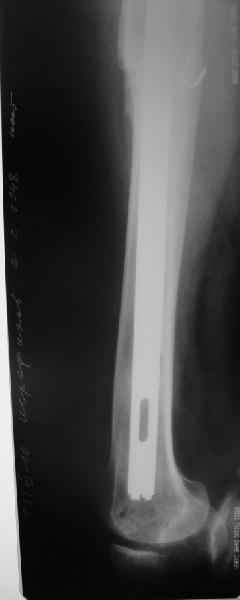

Произведено закрытое удлинение ножки эндопротеза с помощью ретроградного интрамедуллярного стержня. Продолжительность операции 3 часа. Два из них закрытое восстановление длины бедра диистрактором

таз-бедро.

А нельзя ли увидеть и профиль бедра на всем протяжении, т.е. и весь протез, и весь стержень? И фас бы с коленом.

новые снимки